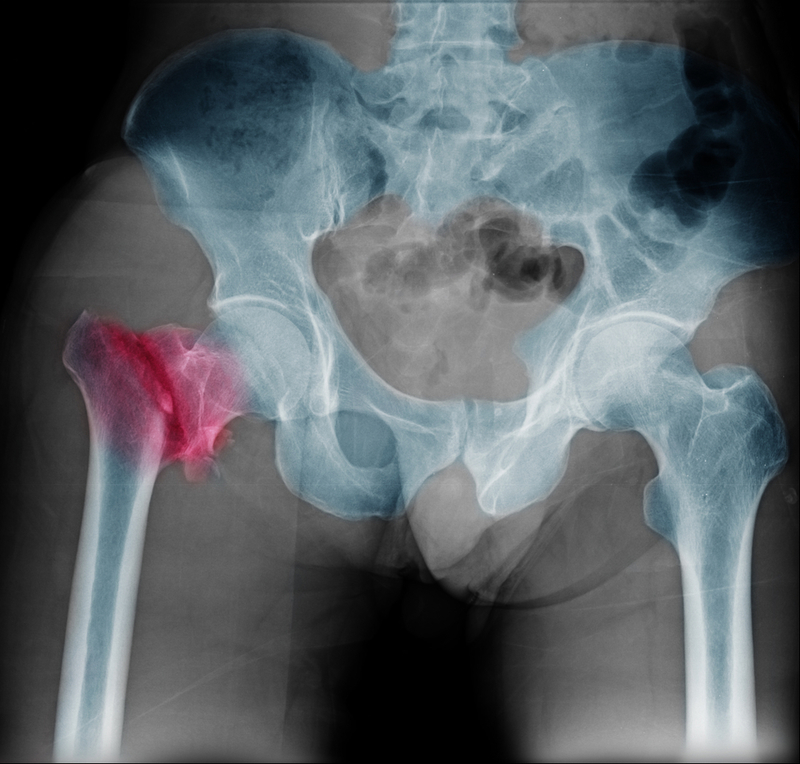

A research was conducted with an aim to find out why even one fracture can lead to others. According to two new studies from UC Davis Health show, breaking a bone causes bone density losses throughout the body, not just close to the site of the fracture, and primarily around the time of the fracture.

Outcomes showed that hip BMD decreased over time for all women in the study, but was greatest for those who had fractured a bone even if the fracture was not near the hip. BMD reductions averaged between .89 and .77 percent per year for those with fractures, and .66 percent per year for those with no fractures. Those losses were greatest within the first two years of a break.

Published in the Journal of Bone and Mineral Research, the second study was conducted using mice with femur fractures and BMD tests in various bones. Once again, bone loss occurred throughout the body, most notably in the spine, and was greatest within the first two weeks of fracture. It also was accompanied by higher levels of inflammatory markers in the blood.